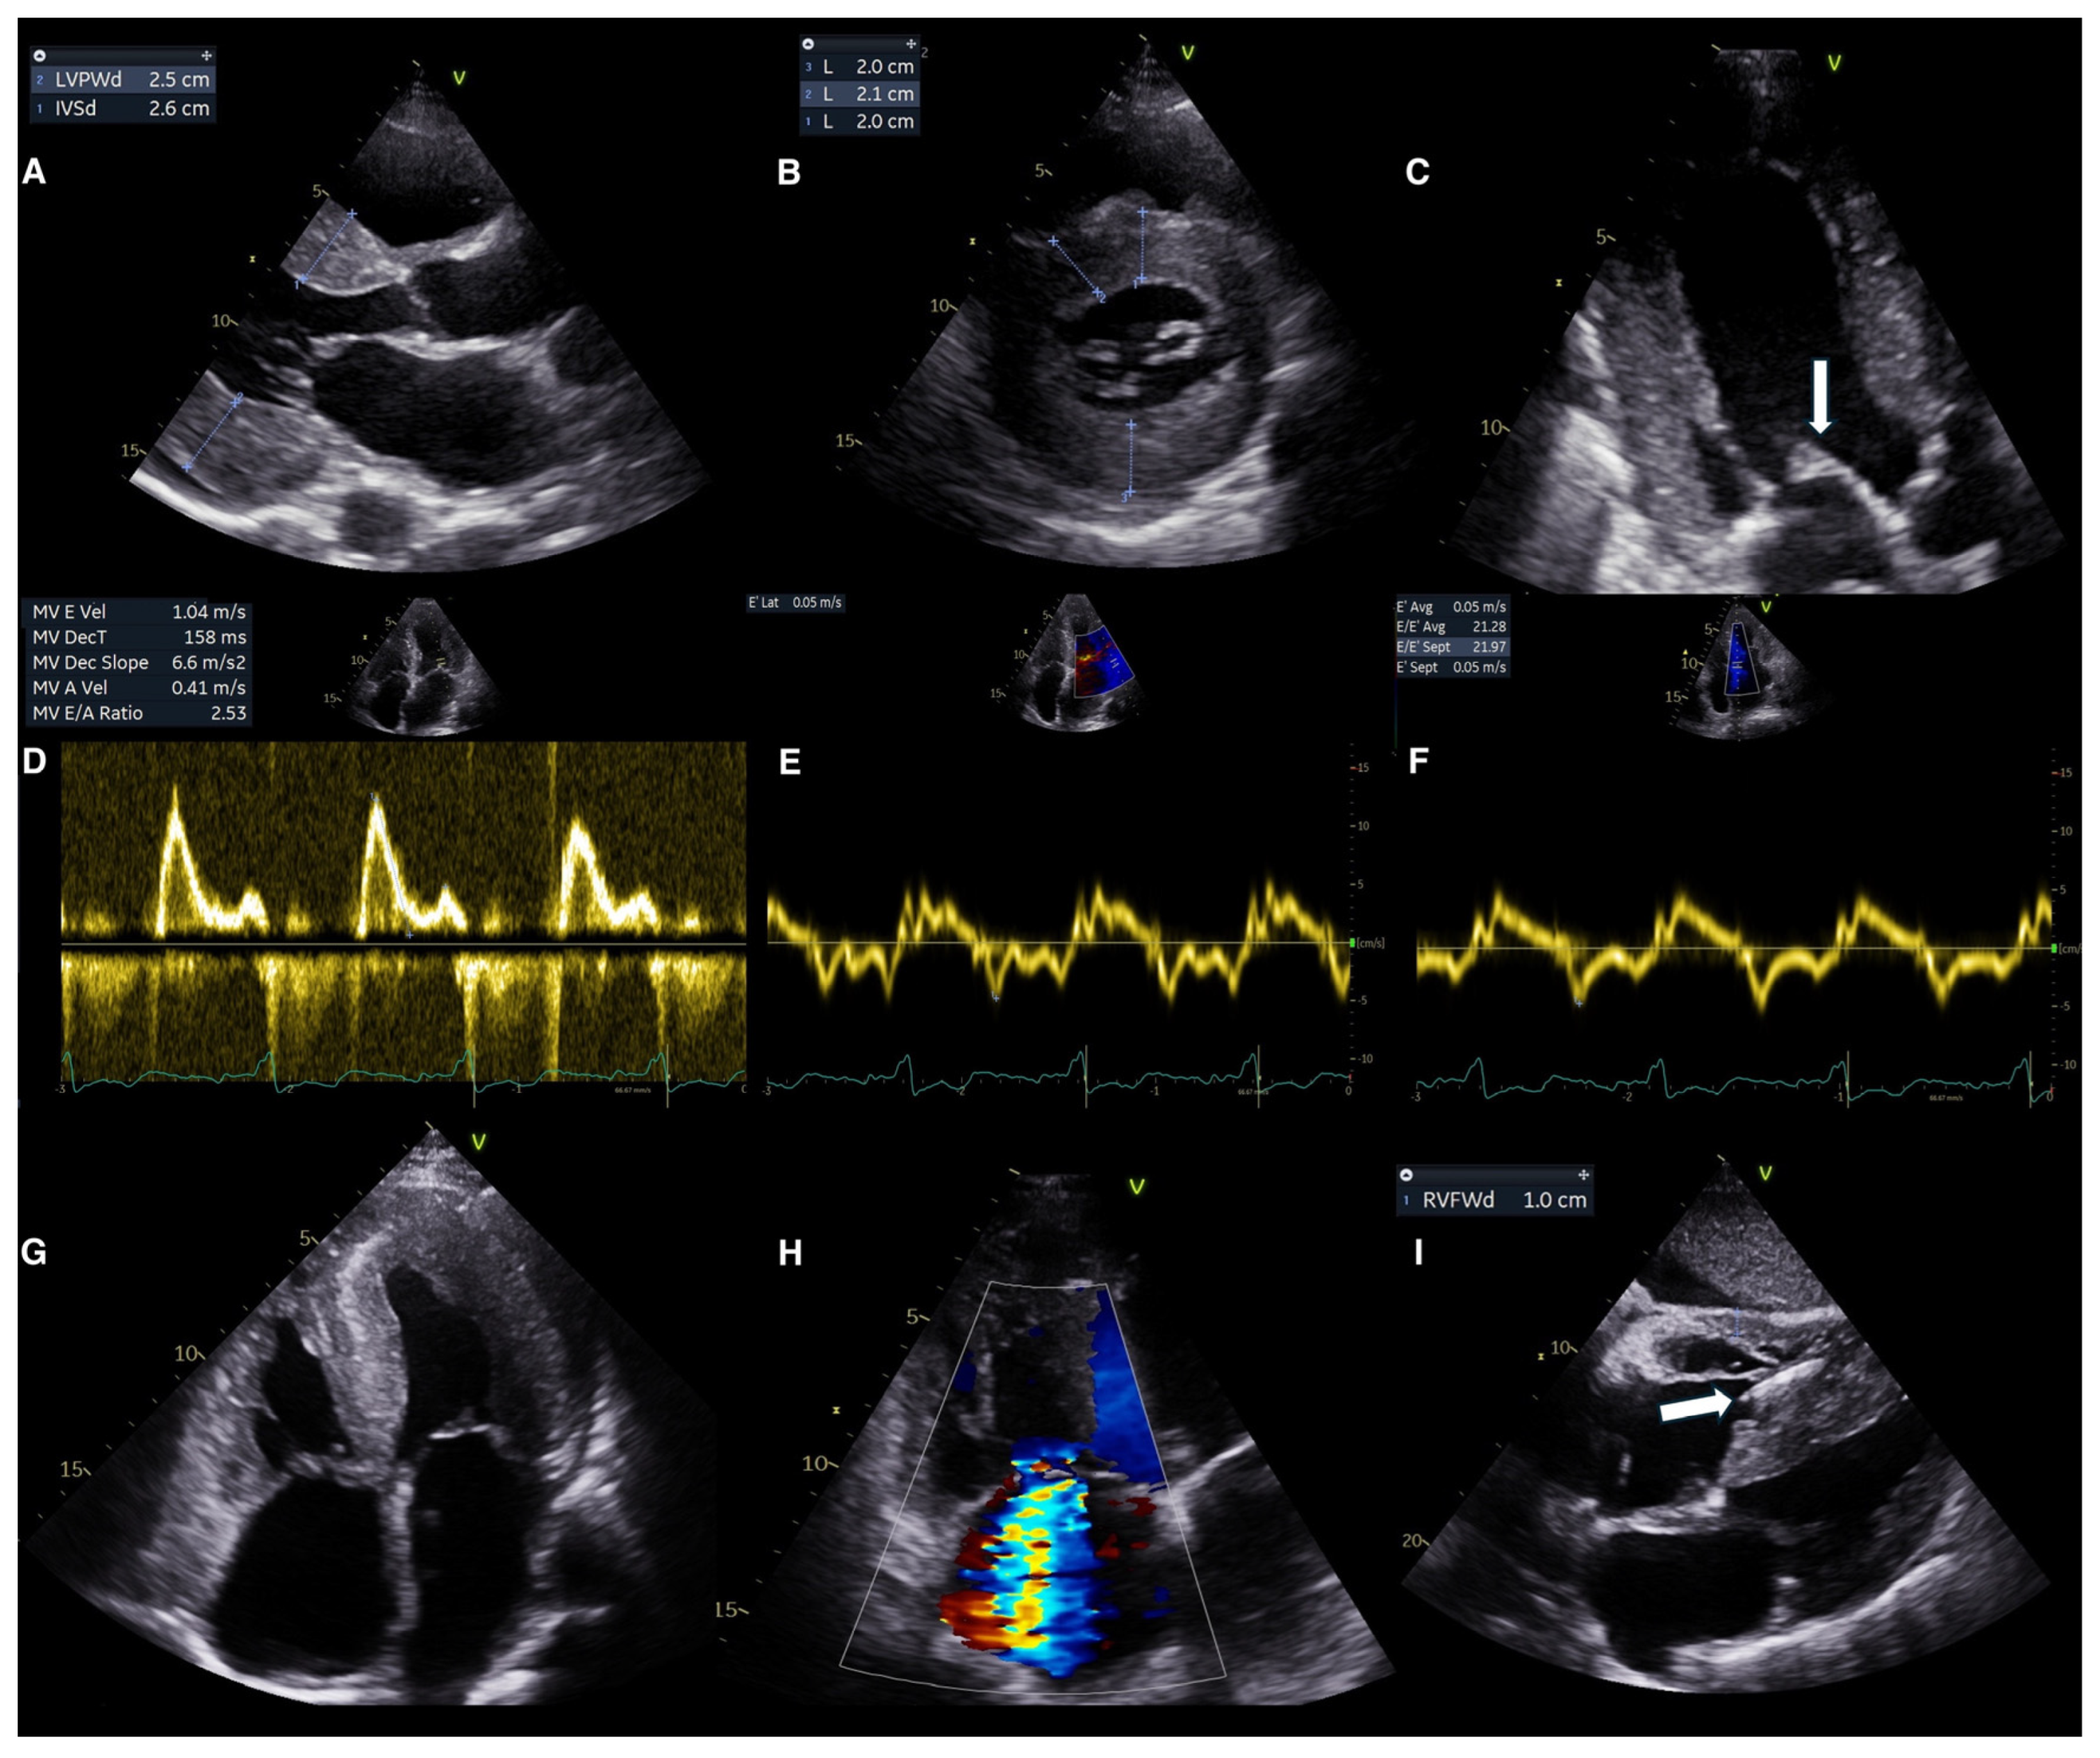

6.1. Echocardiography for Diagnosis

Conventional Echocardiography